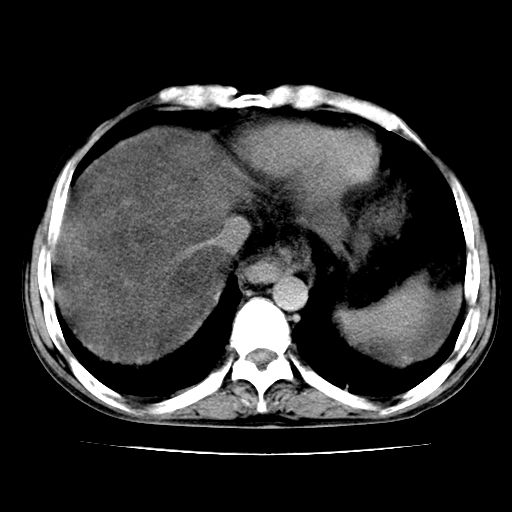

男,55岁,发现“肝硬化”5年,现腰疼、腹胀10余日,巩膜黄染、腹稍胀,肝肋下3指,质硬无压疼,移动性+,血生化:总胆、直胆、间胆均升高。

g1:肝硬化、脾大、腹水。

2:脂肪肝。

肝硬化,脾大,腹水

脂肪肝

脂肪肝性肝病,脾大,建议增强扫描

肝脾肿大,脂肪肝,腹水。建议增强除外肝癌。

1.脂肪肝

3.肝脾肿大

4.肝癌?

肝硬化,脂肪肝,腹水,肝癌